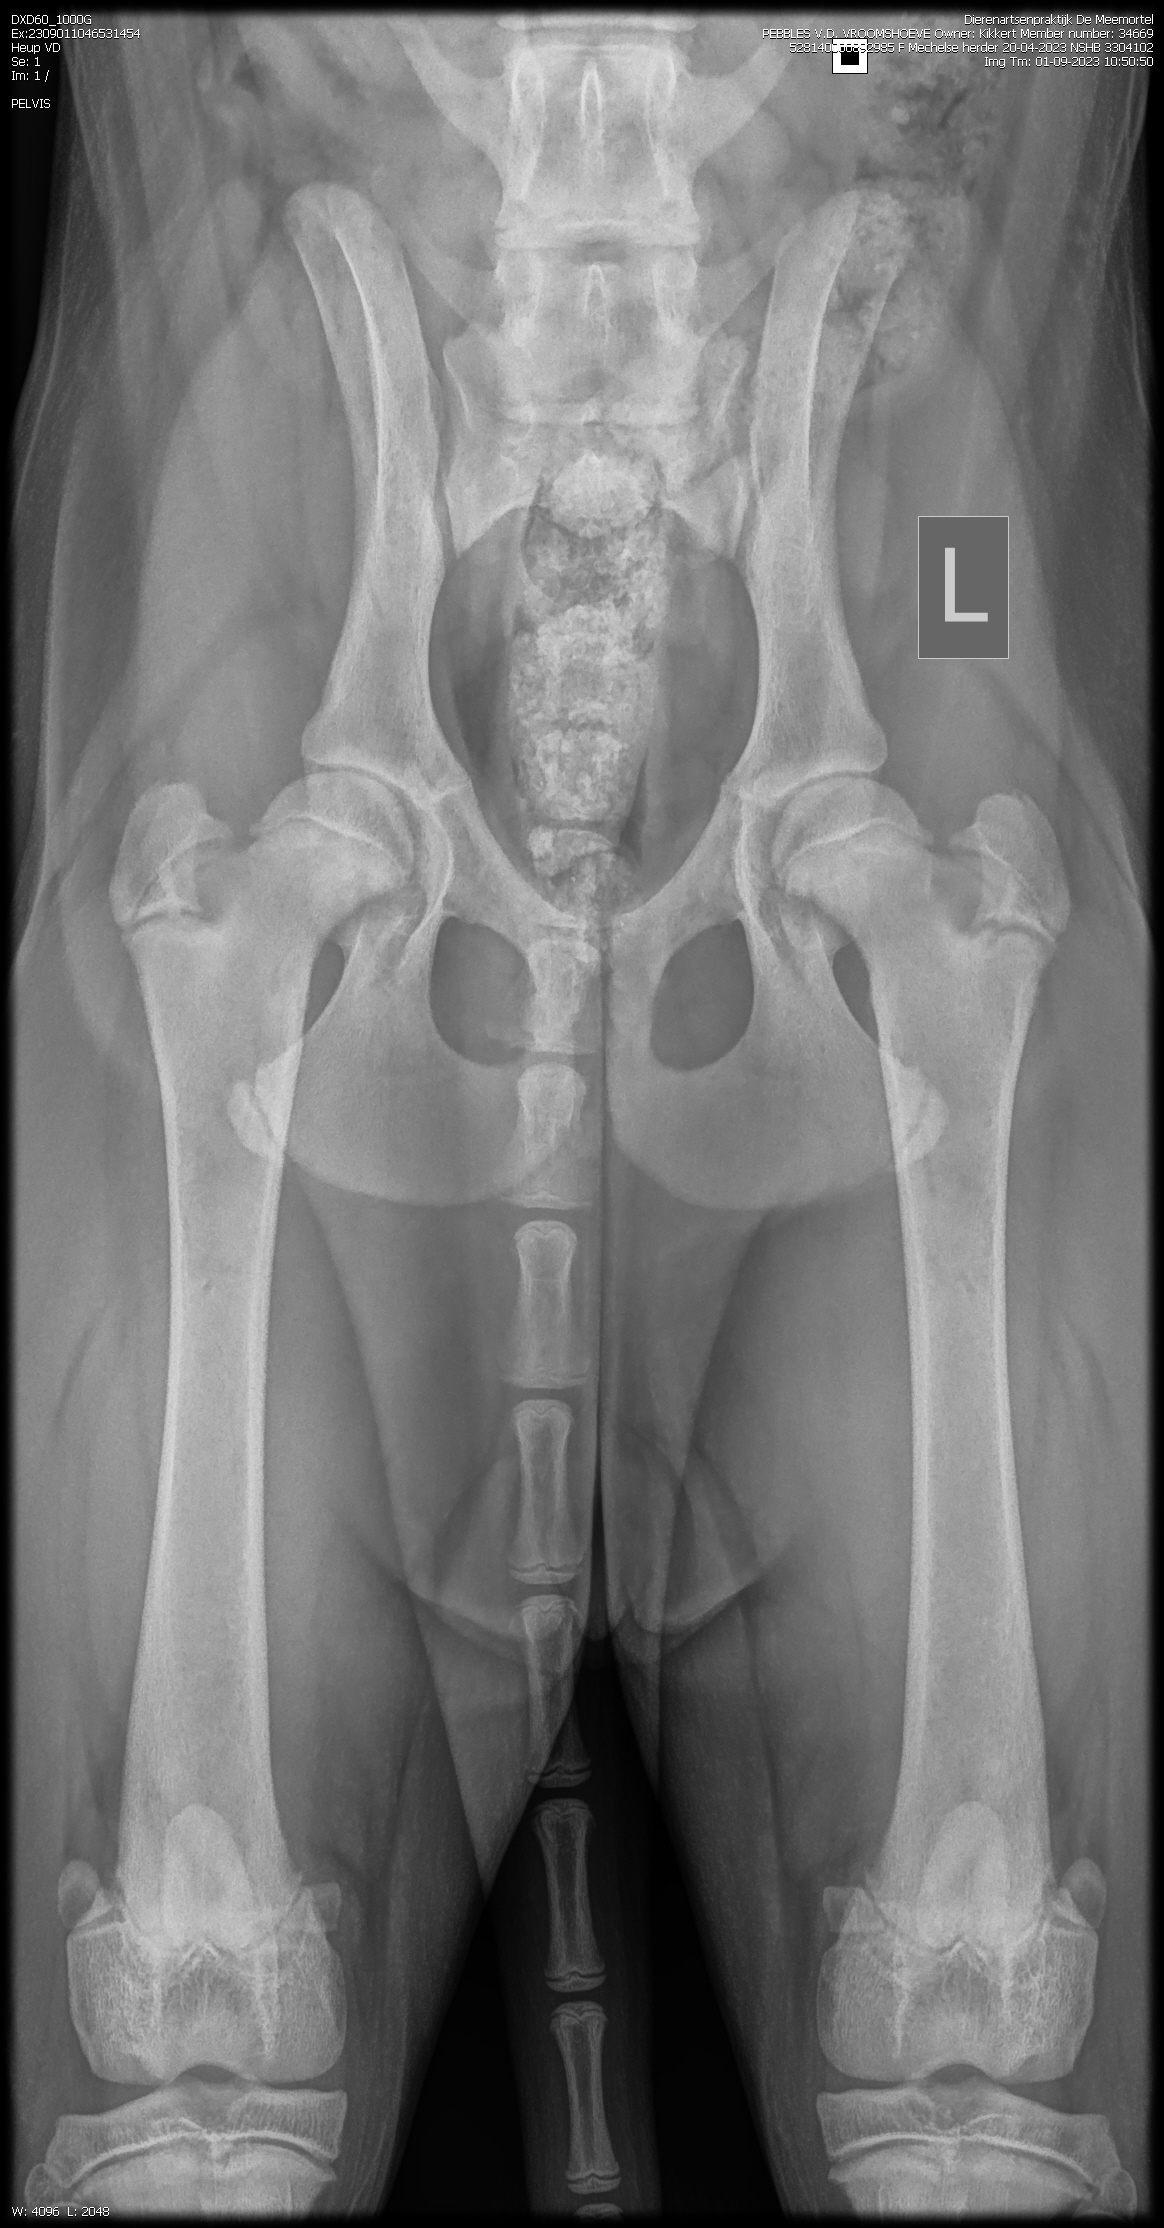

PennHip : Rechts DI 0.19 Links DI 0.16